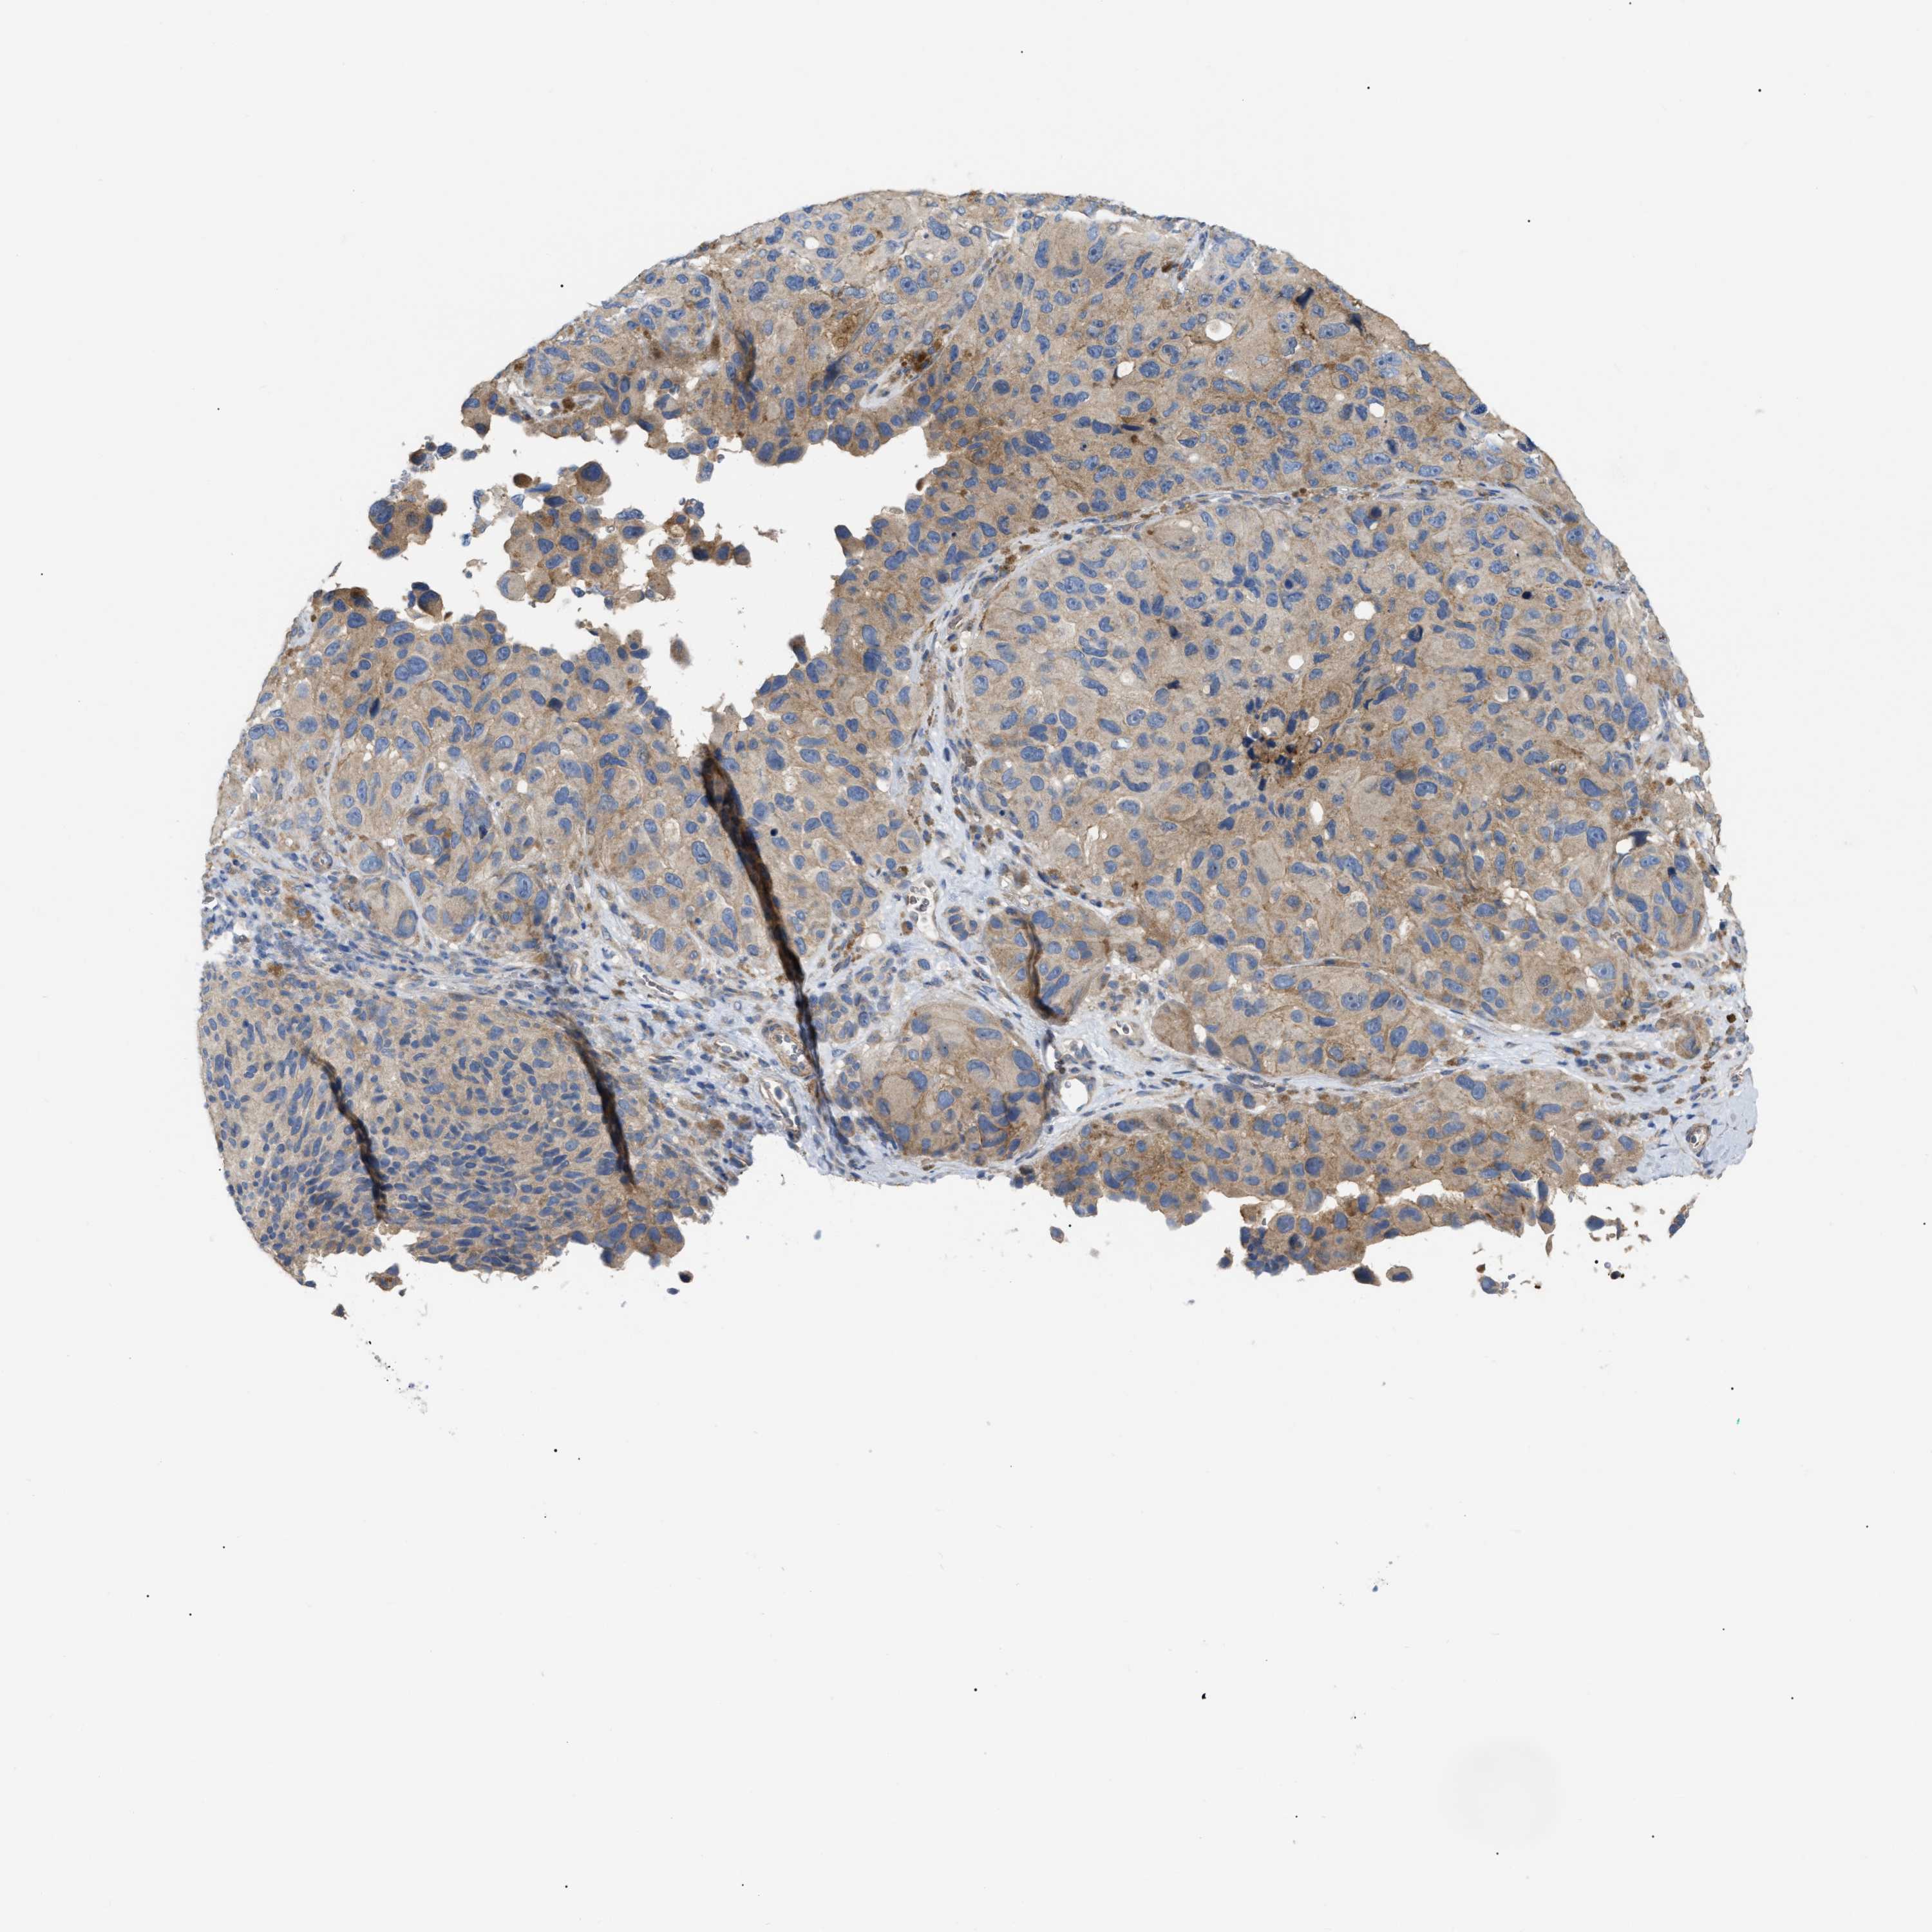

MELANOMA - Protein expressioni

A mouse-over function shows sample information and annotation data. Click on an image to view it in a full screen mode. Samples can be filtered based on level of antibody staining by selecting one or several of the following categories: high, medium, low and not detected. The assay and annotation is described here.

Note that samples used for immunohistochemistry by the Human Protein Atlas do not correspond to samples in the TCGA dataset.

Antibody stainingi

Antibody staining in the annotated cell types in the current human tissue is reported as not detected, low, medium, or high, based on conventional immunohistochemistry profiling in selected tissues. This score is based on the combination of the staining intensity and fraction of stained cells.

Each image is clickable and will lead to virtual microscopy that enables deeper exploration of all samples and also displays staining intensity scores, fraction scores and subcellular localization as well as patient and tissue information for each sample.

Antibody HPA018670

Antibody HPA019570

Staining

High

Medium

Low

Not detected

Intensity

Strong

Moderate

Weak

Negative

Quantity

>75%

75%-25%

<25%

None

Location

Nuclear

Cytoplasmic/membranous

Cytoplasmic/membranous,nuclear

Malignant melanoma, NOS

Malignant melanoma, Metastatic site